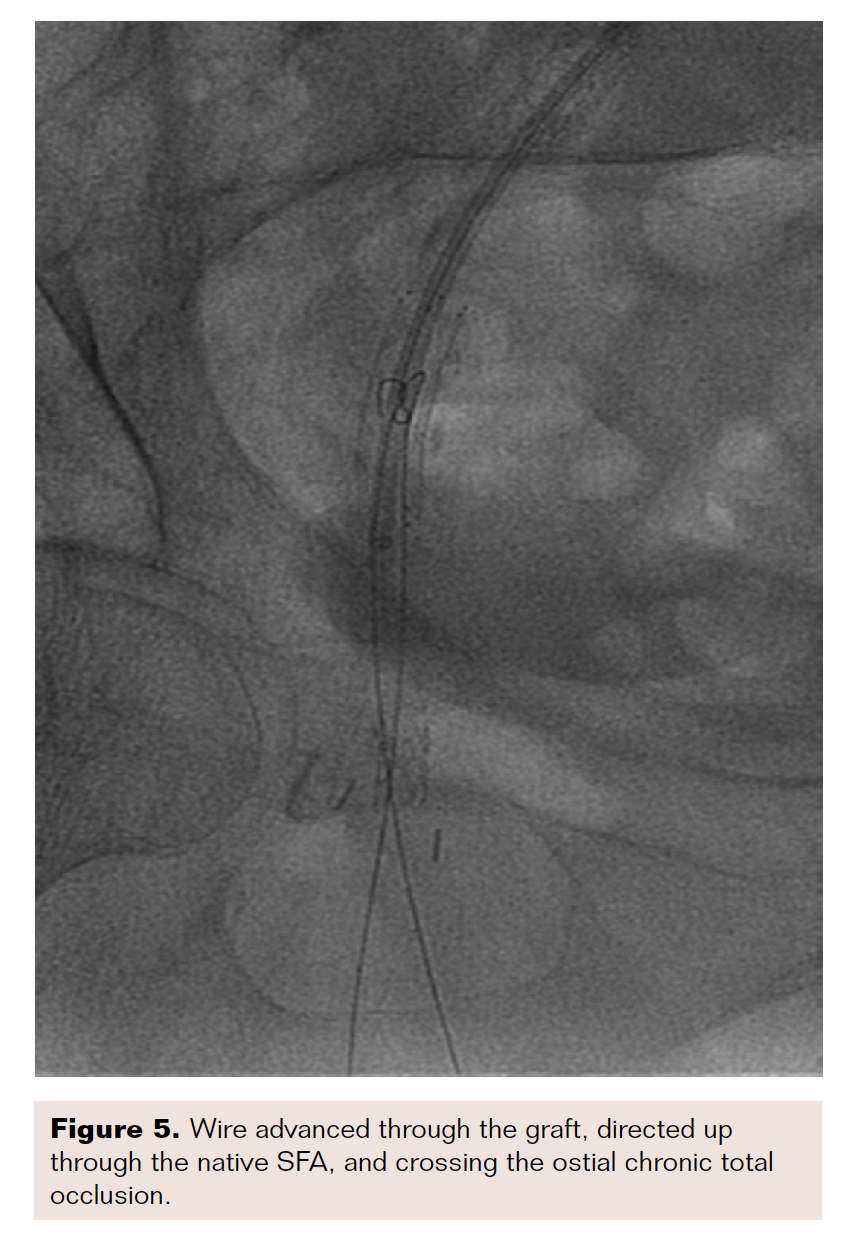

After approximately three hours of acoustic pulse thrombolysis therapy, the patient’s ischemic pain had worsened, and no signs of revascularization were seen. The decision was made to bring the patient back for a repeat angiogram. Subsequent angiography demonstrated no improvement in the thrombus burden and it was decided to proceed with intervention at the native right SFA chronic total occlusion. We used a Quick-Cross catheter (Philips) and V-18 wire (Boston Scientific) and unsuccessfully tried to cross the chronic total occlusion antegrade. We subsequently went through the graft and came retrograde through the distal anastomotic site. We crossed into the common femoral artery and the wire was externalized through the sheath. Atherectomy and stent placement were performed to establish brisk flow to the foot (Figures 5-6).